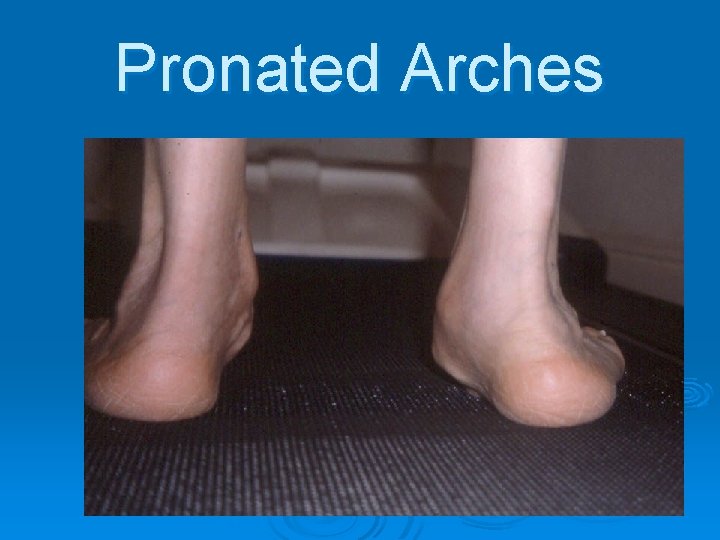

Pronated Arches (Flat Feet)

Pronated Arches

Pronated Arches

Pronated Arches